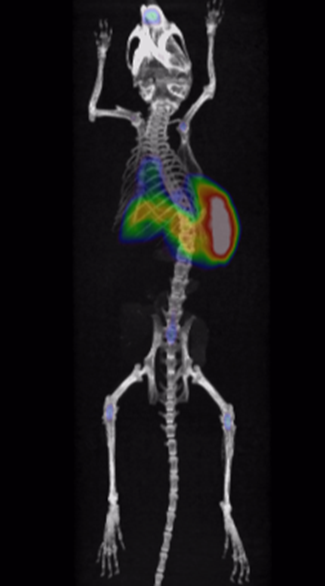

It has been proved that Cu-64-marked nanoantibodies are well-targeting for tumors, with high local uptake and long retention